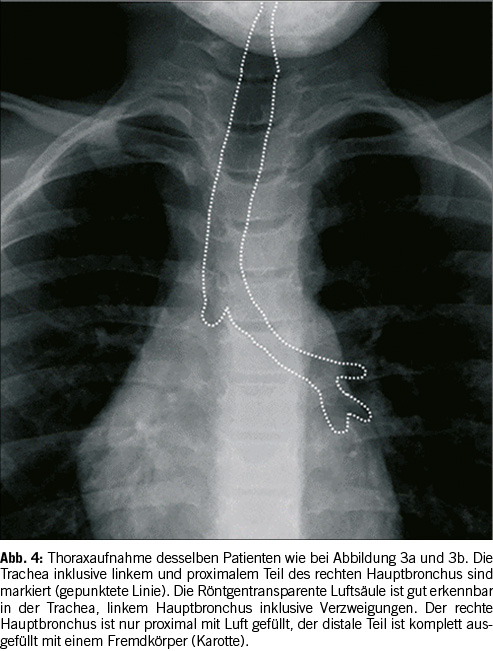

Die Trachea endet in einer achsensymetrischen Gablung, die in die Pulmo dexter und Pulmo sinister übergeht. Sowohl die Trachea als auch die Lungenflügel und das Herz sind auf Röntgenbildern zu erkennen. Auf Abbildung 3a & 3b ist jedoch kein röntgendichter Fremdkörper zu finden. Die indirekten Bildbefunde deuten jedoch auf einen nicht-röntgendichten Fremdkörper im rechten Hauptbronchus hin. Bei der Inspiration sind das Herz und Mediastinum knapp rechts der Mittellinie; während der Exspiration verschieben sich die mediastinalen Strukturen deutlich nach links, mehr als üblicherweise gesehen wird. Das deutet auf ein ‘Airtrapping’ in der rechten Lunge hin, während die linke Lunge eine normale Variabilität der Belüftung bei Inspiration und Exspiration zeigt. Ein zusätzliches indirektes Zeichen eines Fremdkörpers ist das Fehlen der Luftsäule im rechten Hauptbronchus. Bei der Endoskopie wurde ein Teil einer Karotte im distalen, rechten Hauptbronchus gefunden. Diese Karotte hat zudem zu einem progressiven Airtrapping in der rechten Lunge geführt mit progredienter Atemnot. Die Karotte hat über einen ‘Ball-Valve’ Mechanismus bei jedem Atemzug Luft in der rechten Lunge passieren lassen, beim Ausatmen konnte die Luft jedoch nicht entweichen. Diese Situation hätte progressiv zu einer lebensbedrohlichen Situation führen können. Zeitgerechte Erkennung von indirekten Bildbefunden sind dementsprechend von eminenter Wichtigkeit.[8]